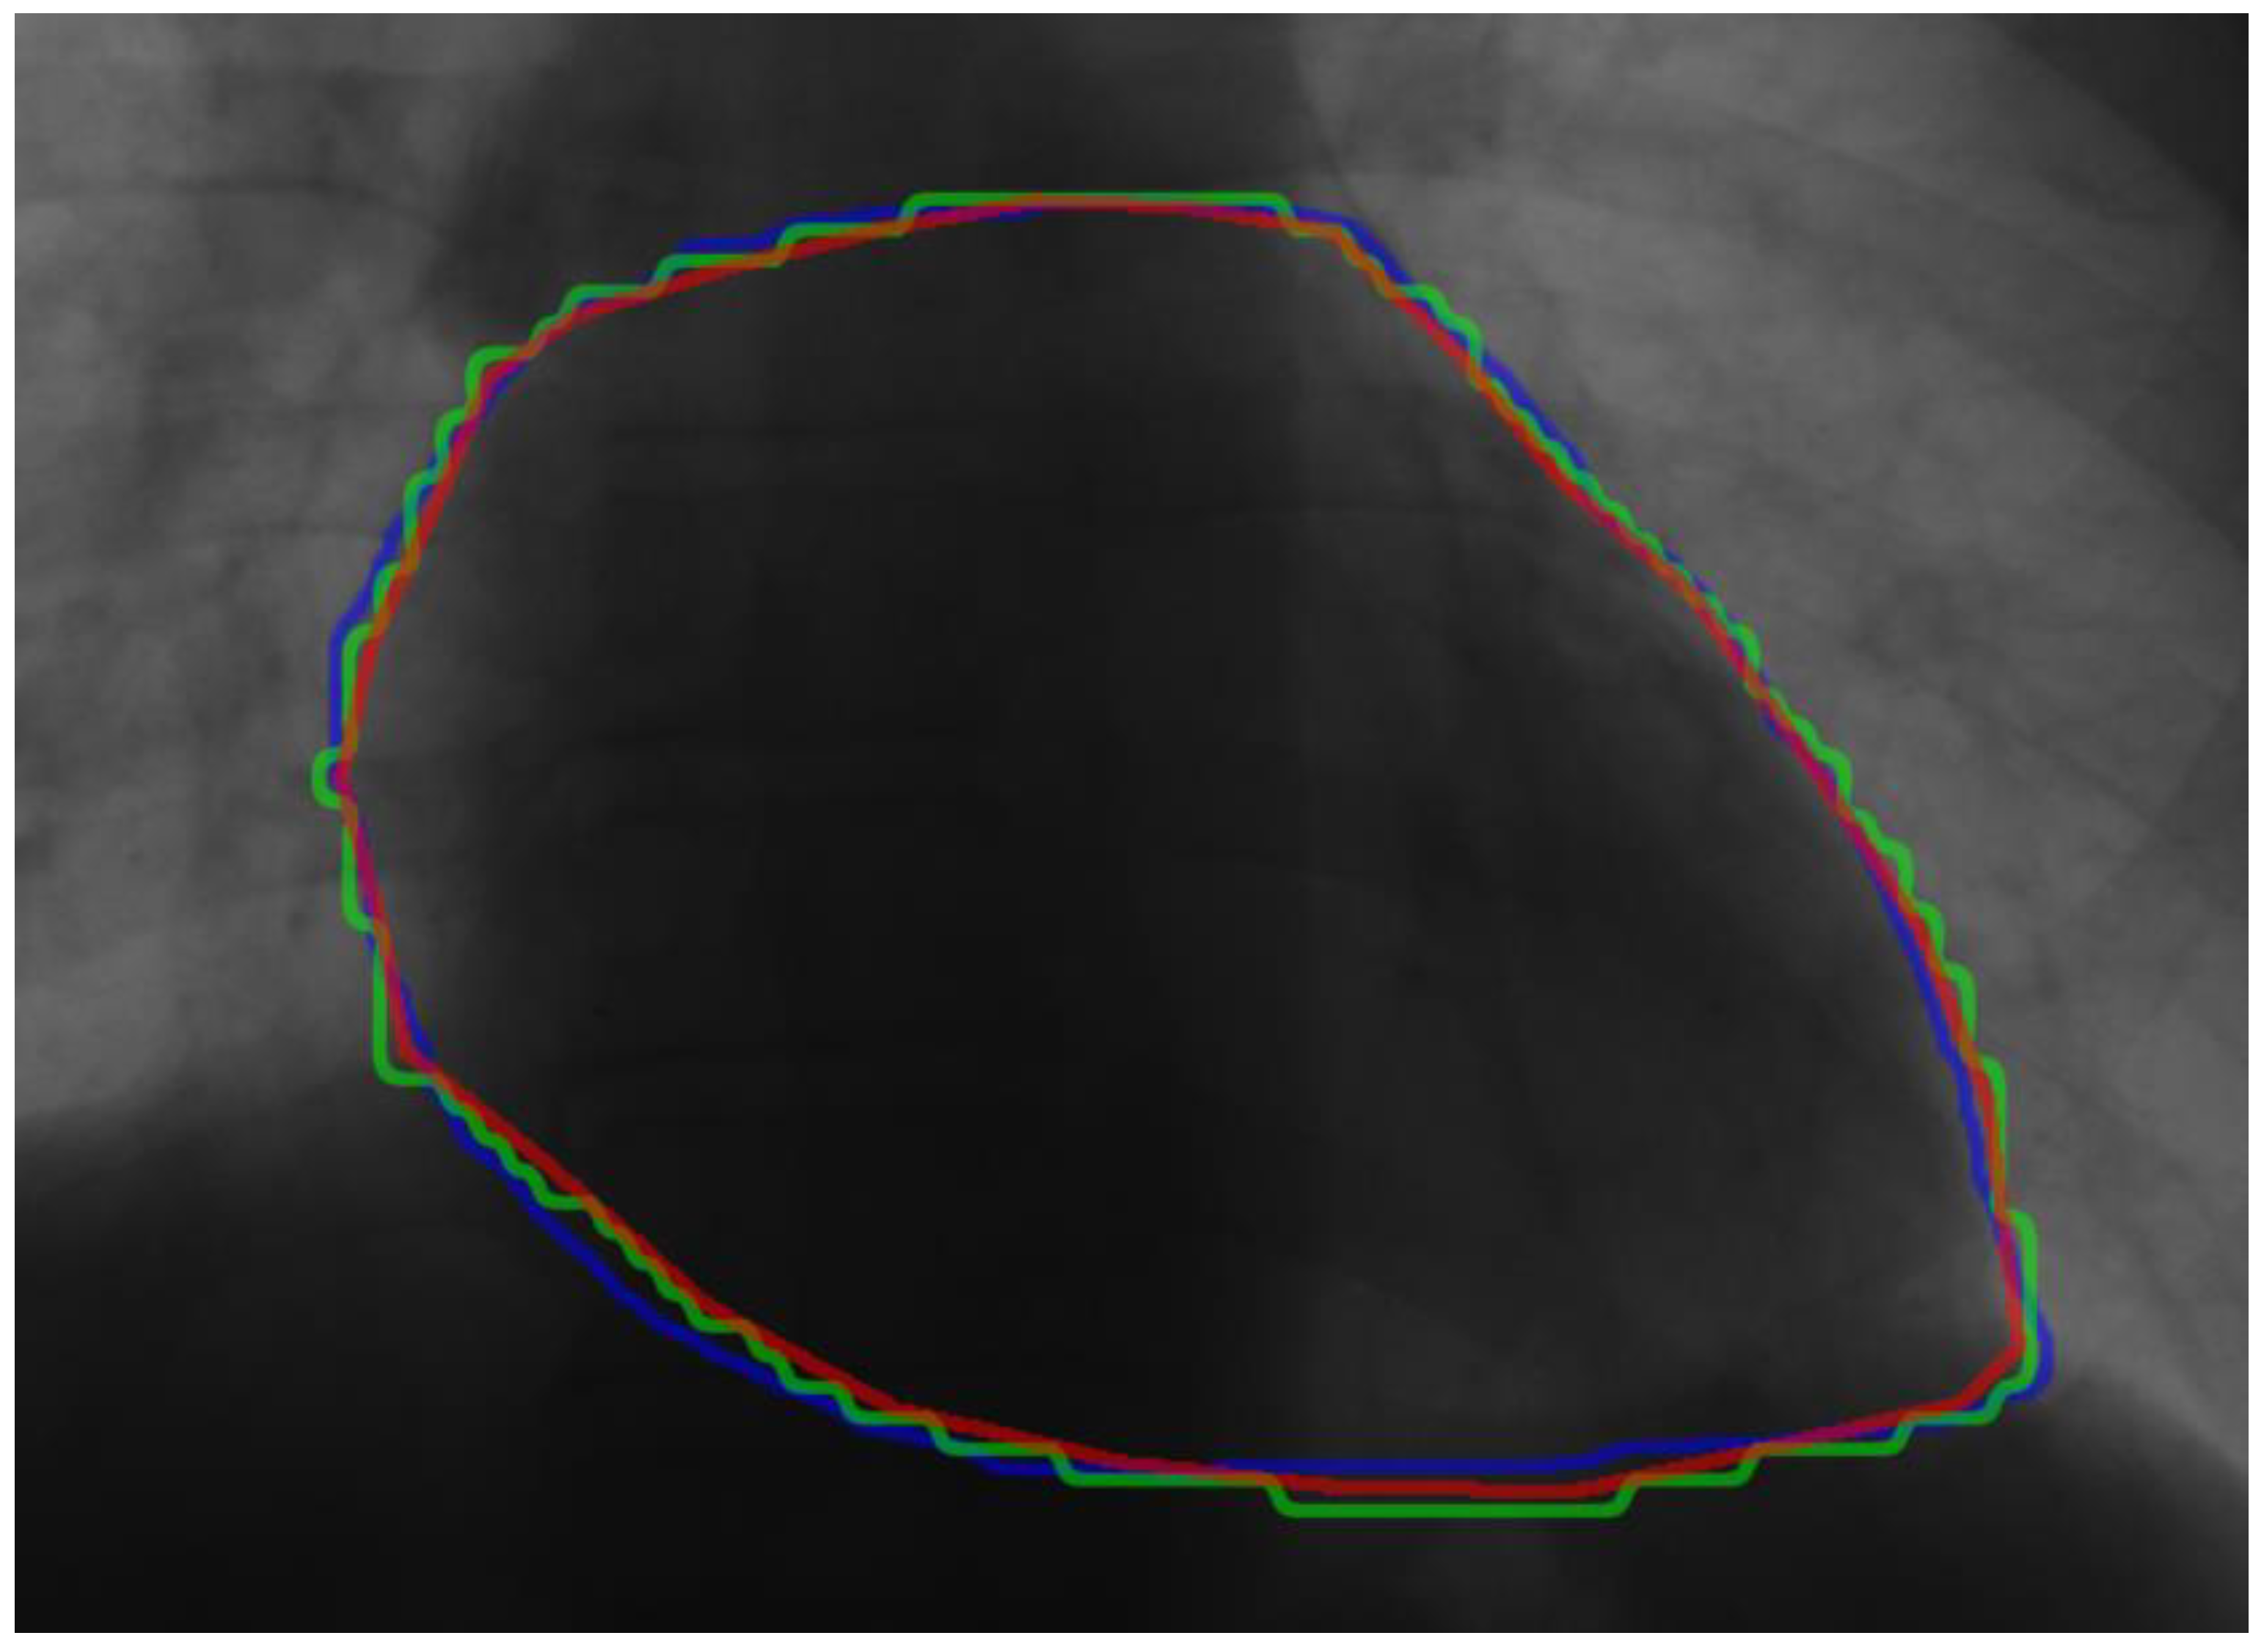

5.4.1. Verification Experiment

- (a)

- Displacement

- (b)

- Rotation